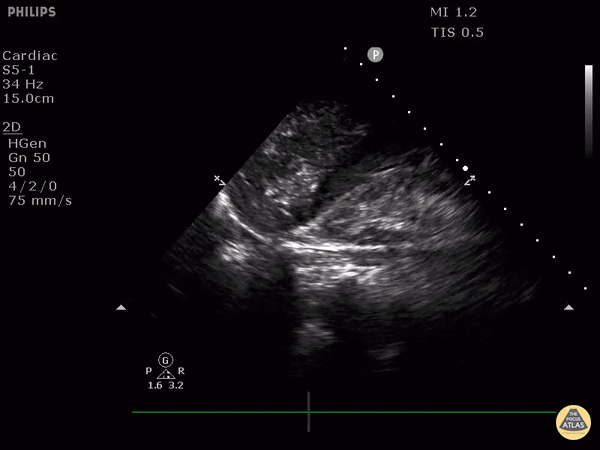

This is a clip demonstrating portal venous gas. Notice air can be seen as hyperechoic signals extending to the periphery of the liver. Air signal can also be seen within the flat IVC. Free intraperitoneal fluid is also present. Patient was ultimately found to have a large diverticular abscess. Image courtesy of Robert Jones DO, FACEP @RJonesSonoEM Director, Emergency Ultrasound; MetroHealth Medical Center; Professor, Case Western Reserve Medical School, Cleveland, OH View his original post here